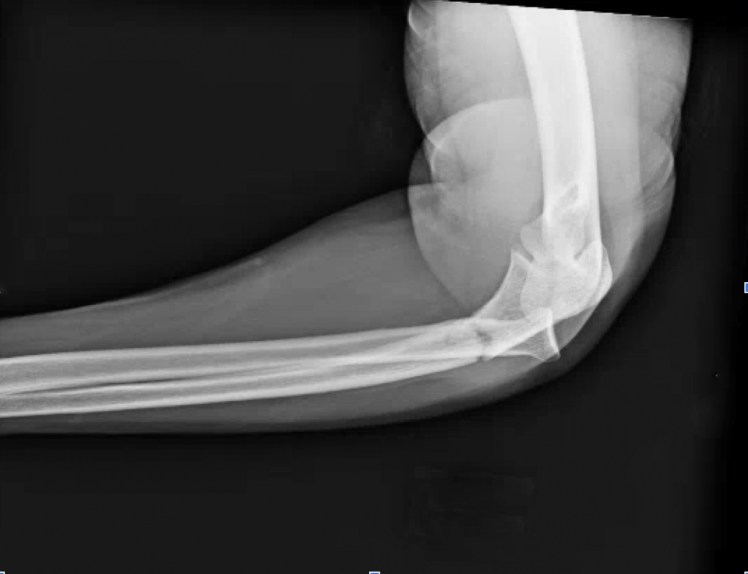

What’s the diagnosis? Gepost op 23 januari 2020 door netwerkvsseh What’s the diagnosis? @emdaily.cooperhealth.org Dit delen: Delen op X (Opent in een nieuw venster) X Share op Facebook (Opent in een nieuw venster) Facebook Delen op LinkedIn (Opent in een nieuw venster) LinkedIn E-mail een link naar een vriend (Opent in een nieuw venster) E-mail Afdrukken (Opent in een nieuw venster) Print Vind-ik-leuk Aan het laden... Gerelateerd